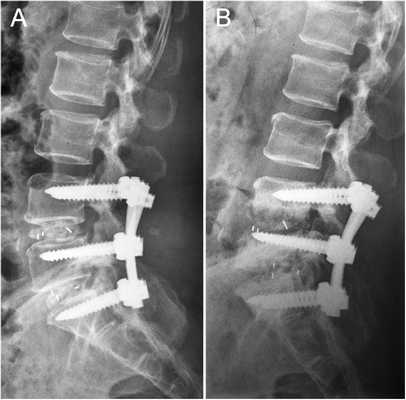

Выпячивание подлежащее хирургическому удалению.

Когда удаляют полностью диск, нередко в освобожденную межпозвонковую полость помещают имплантат, скрепив позвонковую пару стабилизирующей системой. В позвоночник вставлены титановые болты для прочной фиксации поперечного стабилизатора, который в свою очередь будет отвечать за правильное положение относительно хребтовой оси смежных костных тел. Вкручивание болтов осуществляется через дужку в тела позвонков. Современная металлоконструкция обычно представлена динамическими болтами, что позволяет сохранить подвижность прооперированного уровня, максимально приближенную к норме.

Пример такой операции на рентгене.

Через три месяца после операции стабилизации поясничного отдела.